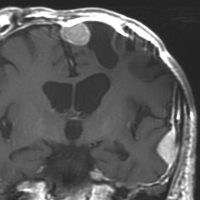

- 下のMRIは66歳の女性に脳ドックで偶然見つかった髄膜腫です.左の写真は1995年,右は2005年です。10年間で全く大きくなっていません

8年間の観察で大きくならなかった髄膜種(左1996年,右2004年)